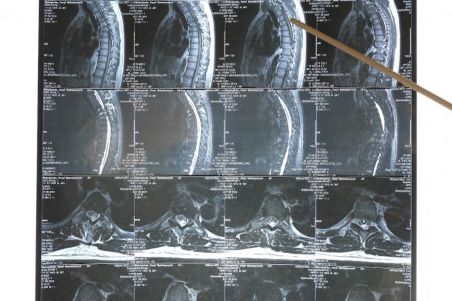

Azərbaycanda alternativ məhkəmə-tibbi ekspertizalar niyə yaradılmır? - VİDEO

Ölkədə hələ də alternativ məhkəmə-tibbi ekspertiza qurumları mövcud deyil...

Xezerxeber.az xəbər verir ki, Tibblə bağlı bütün ekspertiza işlərini Səhiyyə Nazirliyinin tabeliyində fəaliyyət göstərən Məhkəmə-Tibbi Ekspertiza və Patoloji Anatomiya Birliyi həyata keçirir. Yəni, əgər birliyin çıxardığı ekspertiza qərarı sizi qane etməsə, müraciət edəcəyiniz başqa bir ekspertiza mərkəzi yoxdur. Uzun illər hüquq-mühafizə orqanlarında çalışmış hüquqşünas Şamil Paşayev deyir ki, özəl ekspertiza qurumlarının yaradılması zəruridir.

Hüquqşünas deyir ki, xüsusilə həkimlərlə bağlı cinayət işlərində, onların cinayət məsuliyyətinə cəlb edilməsində, sağlamlığa vurulmuş zərərlə bağlı onlardan kompensasiya alınması ilə bağlı məhkəmə işlərində bu problem yenidən aktuallaşır.

Bəzən həkimlər də ekspertizadan narazı qalırlar. Çünki onlar da xəstələrə etdikləri tibbi müdaxilələrin peşəkar mütəxəssislər tərəfindən analiz edilmədiklərini düşünürlər.

Milli Məclisin Səhiyyə komitəsinin üzvü, millət vəkili Pərvanə Vəliyeva da bu sahədə rəqabət olmadığını deyir.

Onun sözlərinə görə, bununla bağlı qanunvericilikdə də dəyişikliklər olunmalıdır. Yalnız bu halda bu sahədə şəffaflıq tam təminə oluna bilər.